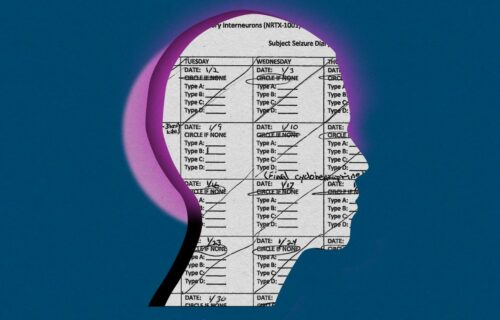

낮과 밤도 구분하기 어려운 58세의 시각장애인 남성이 있었다. 한쪽 망막에 빛을 감지하는 분자를 주입하는 유전자 치료를 받은 후 그는 책상 위에 놓인 노트를 알아볼 수 있었다.

네이처 메디신(Nature Medicine)에 게재한 논문에는 환자가 40년 전 망막의 빛 감지 세포인 광수용체를 파괴하는 퇴행성 질환 색소성 망막염 진단을 받고 시력을 잃은 과정이 기술되어 있다.

의료진은 유전자 치료 기법을 활용해 그의 한쪽 눈에 빛을 감지하는 분자를 주입했다. 빛을 감지하고 빛을 향해 움직이는 단세포 해조류 종에서 추출한 크림슨(chrimson)이라는 유전자를 주입하였다.

유전자를 주입하여 신경절(ganglions)이라는 망막세포를 만듦으로써 뇌에 시각 신호를 보내 빛에 반응할 수 있도록 하는 원리라고 로스카는 설명했다. 이 연구는 프랑스 젠사이트바이오로직스(GenSight Biologics)의 자금 지원을 받았다.

환자는 전용 전자 고글을 써야 한다. 이 고글은 빛의 대비를 포착한 후, 크림슨 분자의 활동을 촉진하는 노란색-주황색 빛의 특정 파장을 이용해 망막에 이미지를 고강도로 투사한다.